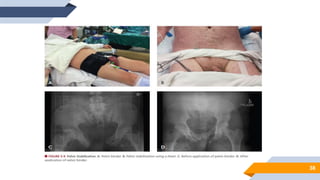

MANEJO

▻ Estabilização mecânica do anel pélvico e contrapressão externa

Rotação interna dos membros inferiores

Imobilização da pelve com um lençol ou atadura a nível dos trocanteres

maiores do fêmur

Tração longitudinal nos casos de lesões por cisalhamento vertical

MANEJO ▰ Ressuscitação volêmica ▰Controle da hemorragia ▻ Estabilização mecânica do anel pélvico e contrapressão externa 37 Rotação interna dos membros inferiores Imobilização da pelve com um lençol ou atadura a nível dos trocanteres maiores do fêmur Tração longitudinal nos casos de lesões por cisalhamento vertical